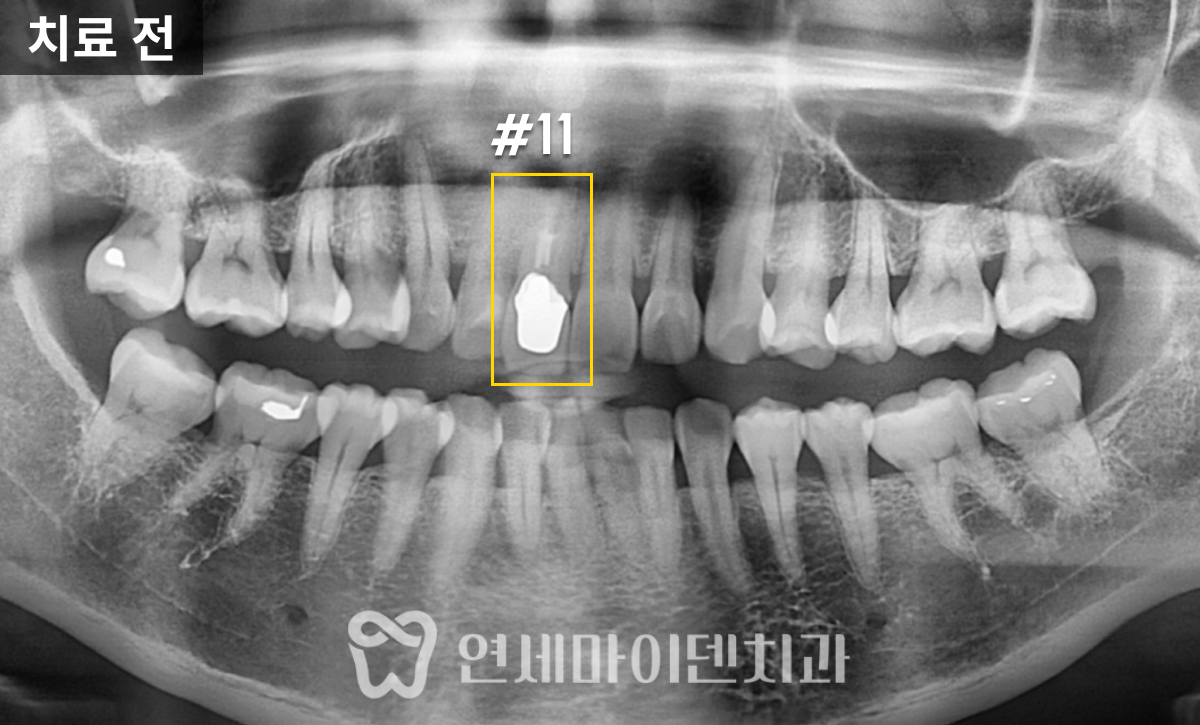

■ 환자의 주요 증상과 진단 과정

이 환자분은 '예전에 신경치료를 받았던 왼쪽 위 어금니쪽이 시린 증상이 있고 아프다'며 내원하셨는데요.

두 개의 치아 모두 불편함이 있었고, 모두 치료를 받은 지 꽤 되었으며, 염증이 있는 상태였습니다.

정확한 진단을 위해 환자분의 덴탈 히스토리, '언제 치료를 받으신 건지', '언제부터 통증이 있었는지'를 물어보고, '악화 요인이 무엇인지'를 정확히 파악하려 했습니다. 엑스레이나 CT도 중요하지만, 이런 덴탈 히스토리까지 진단에 포함되어야 환자분의 불편함을 정확하게 해소할 수 있습니다.

■ #25번, 첫 번째 치아 치료 - 재신경치료

살펴보니 과거에 받으셨던 신경치료의 퀄리티가 아쉬운 부분이 있었습니다.

신경관뿌리까지 치료가 되어있지 않고, 중간에 갭이 보였습니다.